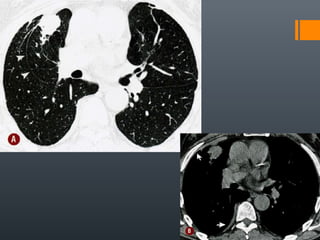

O documento discute vários conceitos radiológicos incluindo consolidação, atelectasia, nódulos, pseudocavidades e padrões intersticiais, fornecendo definições, sinais e diagnósticos diferenciais para cada tópico. Ele também discute a redução da atenuação pulmonar e fornece um link para mais informações.